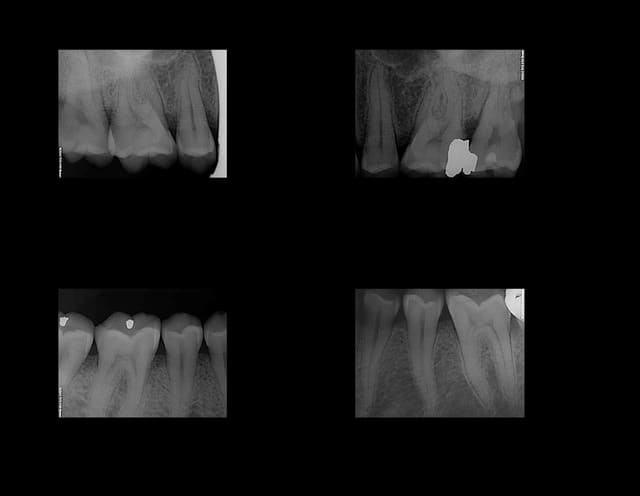

Nouvelle Patiente Mrs X présentant des signes d'appels simultanés sur 36 46. Suspicion d'atteinte pulpaire donc 2 rétro alvéolaires gratuites.-))

Diagnostic : pulpite sur 46 et 4 eme ° sur 36.

Dans le souci de ne pas irradier la patiente inutilement aucune autre radiographie gratuite d'un autre secteur n'est réalisée. Qui plus est le docteur chicot 29 étant équipé d'un capteur kodak 6100 ne peut pas réaliser de mordus rétro coronaires. Le Dr chicot 29 ayant une demi-heure devant lui réalise l'endo de 46 et cote donc Z6 fois 2 + SC 34 et met la patiente sous atb pour le 4 eme de la 36. Ce faisant il fait économiser à la caisse une C à 23 euros.-))

Meme en mode Bw rétro coronaire (capteur horizontal) il est impossible d'avoir toutes les molaires et prémolaires avec un kodak 6100 meme avec 4 clichés (Je ne comprend pas d'ailleurs le capteur semble couvrir toutes les dents) Il manque la 7 ou la 4. 8 clichés sont donc nécessaires (contre 12 en rétro alvéolaires capteur vertical).

Une rétro alvéolaire a été réalisé en sus pour la 37 bien qu'elle ne présente pas de "signes d'appels". Une magnifique endo révélée comme d'hab, le patient est éclairé quant à la survenue d'un éventuel problème. On peut se poser des questions également sur la pertinence des micro classes 1 amalgame sur 46 et 47 a moins que ce soit la conséquence d'un comportement "imaginatif " cher à Catherine M pour rentabiliser les soins opposables.